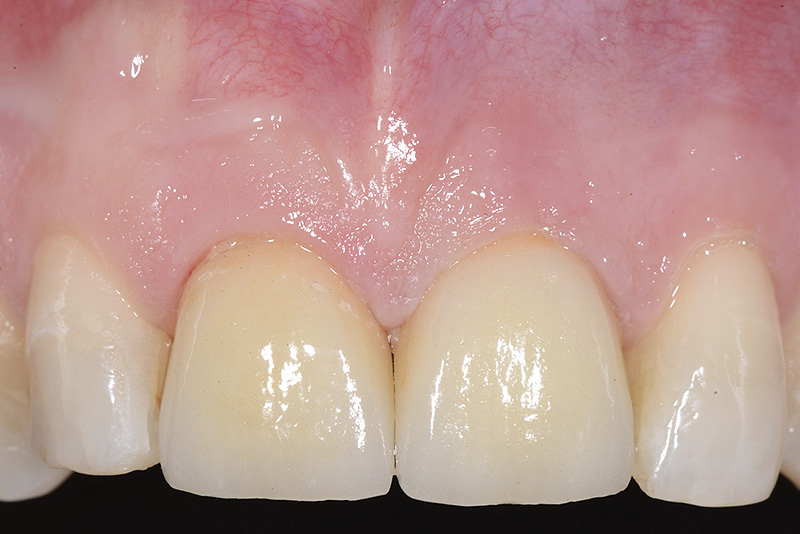

PREMESSA: in seguito all’estrazione dell’incisivo laterale superiore di destra, resasi necessaria per cause batteriche, si decide di affrontare il caso con il posizionamento di un impianto in sostituzione dell’elemento mancante dopo guarigione del sito infetto. Con tecniche rigenerative sia dei tessuti ossei mancanti a causa dell’infezione pregressa, sia dei tessuti gengivali che appaiono inizialmente troppo spostati in alto, si ripristina una corretta morfologia delle parabole (contorni) gengivali e delle papille interdentali (triangoli di gengiva tra due denti vicini).

Vengono utilizzati 2 tipi di provvisori: il primo, cementato ai denti vicini, viene utilizzato dal momento dell’estrazione del dente fino ad impianto osteointegrato (circa 6 mesi); il secondo, avvitato direttamente all’impianto, ha una funzione di prova estetica ma soprattutto di guida per la maturazione dei tessuti gengivali peri-implantari portandoli verso la maturazione completa prima di posizionare la corona finale in disilicato di litio.